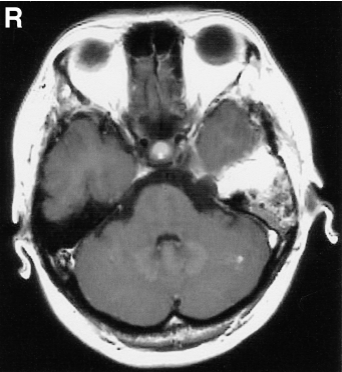

38岁女性绫子因左侧面部感觉异常就医。磁共振成像显示为哑铃状肿瘤,明显增强(图1上排)。肿瘤较实,主要位于左中颅窝,三叉神经根是肿瘤的明显起源,并经Meckel’s腔延伸至后窝。根据我们对三叉神经鞘瘤的分类,诊断为MP型,代表三叉神经鞘瘤的中后颅窝位置。肿瘤大小2.5×1.8×2.0cm。由于患者要求,最终行GKR。整个肿瘤在50%等剂量体积内(图2)。最大辐射剂量为28Gy,边际辐射剂量为14Gy。然而,随访MRI显示肿瘤囊肿形成,GKR后15个月肿瘤增大。患者于GKR术后18个月开始主诉左外展神经麻痹导致左侧面部疼痛和复视,转院治疗。

入院时,MR示左侧中后颅窝一哑铃状肿瘤,t1低强度,t2高强度。肿块内有多个囊肿,实性部分增强均匀。肿瘤后部形成囊肿,囊部强化,与后颅窝硬脑膜连续,明显压迫脑干,肿瘤大小为4.5×2.5×2.5cm(图1下排)。

术后因左外展神经麻痹缓解,复视消失,但面部疼痛加重,予卡马西平治疗。术后MR成像未见肿瘤残留(图2、5)。